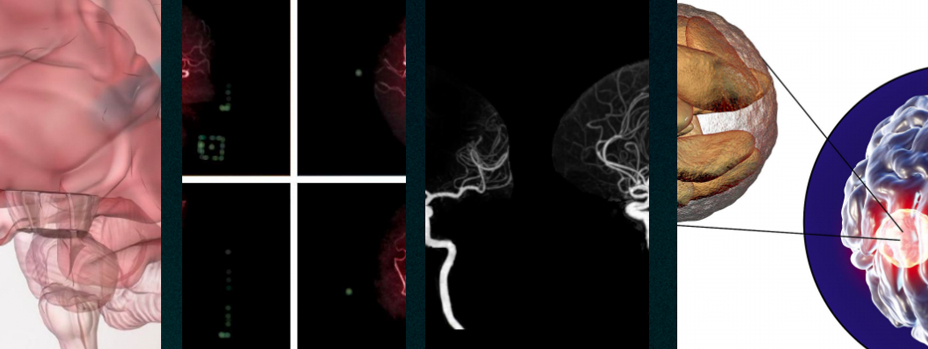

· 腦血管疾病

機制:臭氧可以改善血液流動性,增加紅細胞的攜氧能力,促進腦部血液循環(huán),減少缺血再灌注損傷。

腦梗死:通過靜脈注射臭氧,可以改善腦部血液循環(huán),減少腦組織的缺血損傷,促進神經(jīng)功能的恢復。

腦出血 : 臭氧可以減輕腦水腫,減少炎癥反應,有助于穩(wěn)定患者病情,促進康復。